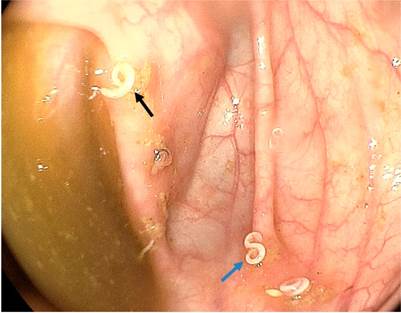

En cuanto a las características morfológicas de las uncinarias, se ha descrito que son parásitos cilíndricos, de color blanco, de entre 10-15 mm de longitud, con su extremo anterior generalmente recto y su cuerpo en curva amplia (con forma de C para el Ancylostoma duodenale y una ligera curva en sentido inverso a la parte anterior, que da apariencia de S para el Necator americanus). Estos hallazgos muy similares a los vistos en la Figura 1 del caso en discusión.

Figura 1 Múltiples uncinarias en el colon derecho. La flecha azul muestra la característica forma en S del N. americanus, mientras que la flecha negra señala la característica forma en C del A. duodenale.

Morphologically, hookworms have been described as white cylindrical parasites that measure 10 to 15 mm in length. Their anterior ends are generally straight, but their bodies are curved: wide C-shaped curves for Ancylostoma duodenale but slight S curves in the opposite direction for Necator americanus. These findings are very similar to those seen in Figure 1 of the case under discussion.

Figure 1 Multiple hookworms in the right colon. The blue arrow shows the characteristic S-shape of N. americanus, while the black arrow indicates the characteristic C-shape of A. duodenale.